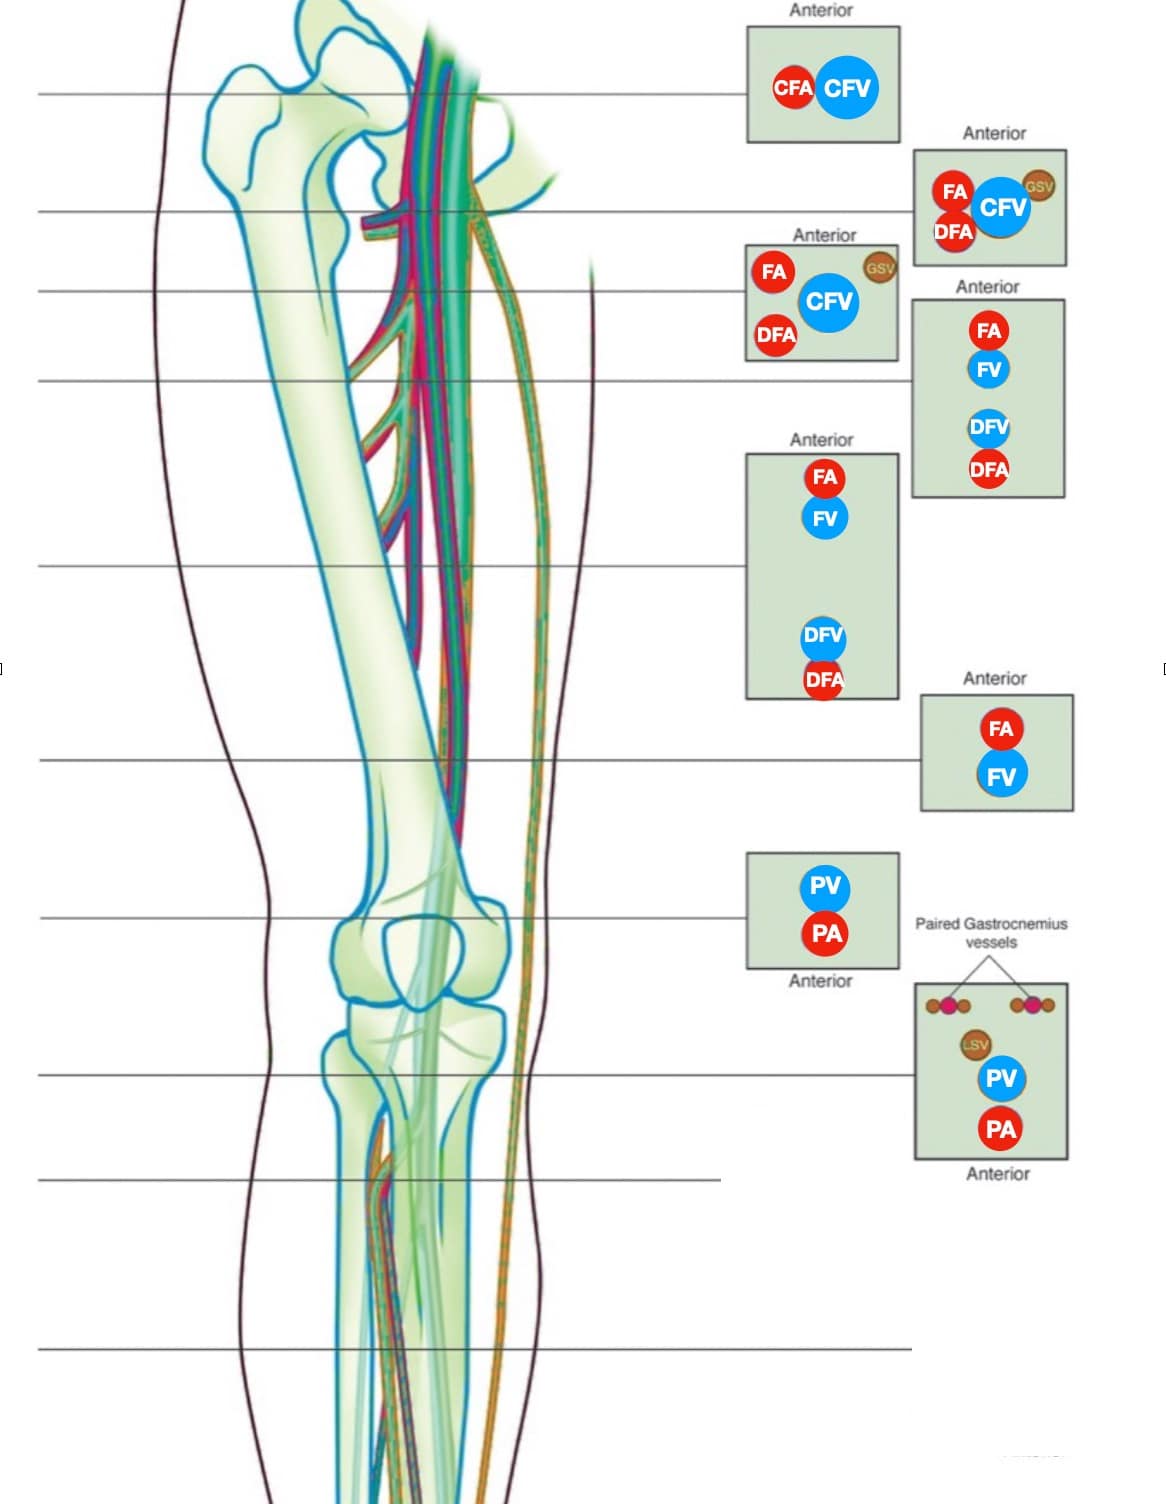

LE Venous Anatomy

The proximal LE venous system consists of the external iliac vein (EIV), CFV, FV, profunda femoral vein (PFV) and PV (Figure 2).

Figure 2. The lower extremity (LE) venous system. Note that the direction of the proximal examination goes in a caudal and medial direction following the veins.

CFA = common femoral artery, CFV = common femoral vein, DFA = deep femoral artery, DFV = deep femoral vein, FA = femoral artery, FV = femoral vein, GSV = greater saphenous vein, LSV = lesser saphenous vein, PA = popliteal artery, PV = popliteal vein